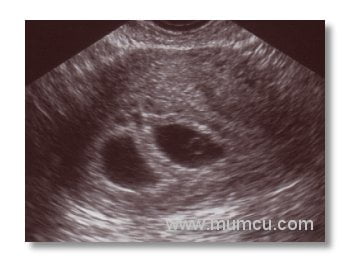

5 haftalık gebelikte gestasyonel kese

Vajinal ultrasonografi